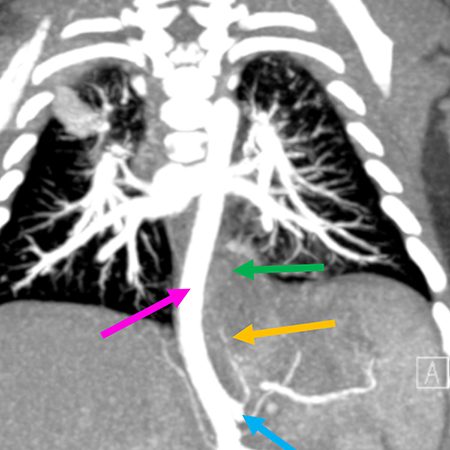

Case of the Month

Clinical History: A 2-month-old male child was found to have a thoracic mass on prenatal ultrasound. Postnatal imaging was consistent with pulmonary sequestration. Computed tomography of the chest showed a 3.9-cm posterior mediastinal mass (Figures 1 and 2) extending into the infra-diaphragmatic region displacing the aorta without luminal compromise. Pulmonary sequestration was felt to be the most likely diagnosis, with retroperitoneal neuroblastoma as the less likely differential diagnostic consideration. The mass was surgically excised. H&E images are shown in Figures 3-6.